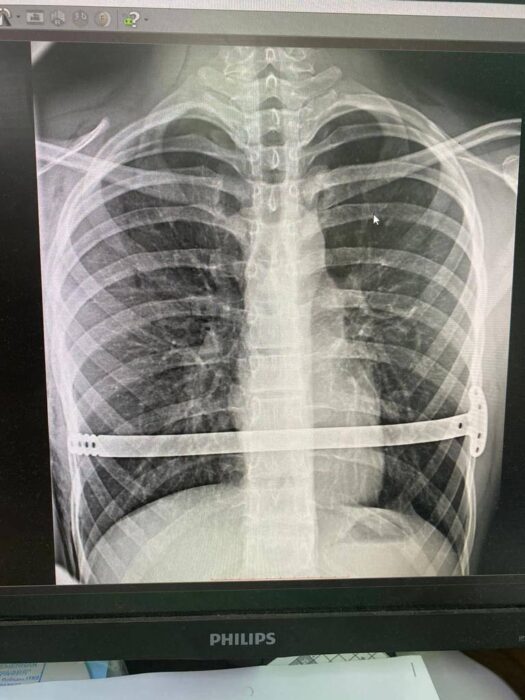

Как объясняют врачи Оренбургской областной детской клинической больницы, порок развития у подростка начал прогрессировать в пубертатный период. К 16 годам воронкообразная деформация грудной клетки достигла 2 степени и имела симметричную форму. Мальчик обратился к медикам с жалобами на одышку, слабость и учащенное сердцебиение. Он добавил, что деформация усилилась в течение последнего года.

Юному пациенту провели обследование: сделали компьютерную томограмму, ЭКГ, спирометрию. В результате врачи пришли к решению о необходимости провести операцию Насса. Хирургическое вмешательство проводится с использованием малоинвазивной методики, которая позволяет устранить воронкообразную деформацию грудной клетки.

Коррекция деформации включает три этапа: установка пластины, период ее ношения и удаление пластины. Подросток прошел первый этап, операция прошла хорошо и послеоперационный период был без осложнений, добавили врачи ОДКБ. Спустя неделю мальчика выписали домой. В течение некоторого времени ему нужно будет поберечься.